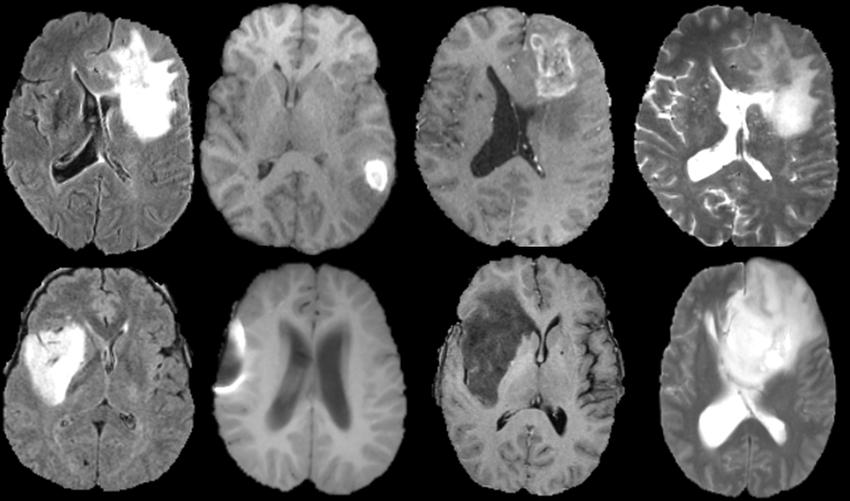

However, the size of the dataset with annotations has a significant impact on the performance of deep learning approaches. Given the complexity and abundance of medical data, it is very difficult to label a significant number of medical pictures. In this study, the authors present an innovative transfer learning-based active learning framework to lower the annotation cost while retaining the robustness and stability of the model performance for classifying brain tumors. In this retrospective study, the authors utilized the magnetic resonance imaging (MRI) training dataset of 203 patients and the validation dataset of 66 patients as the baseline to train and fine-tune our model. The BRATS 2019 dataset [33, 34] which contains 335 individuals with brain tumor diagnoses, served as the basis for this study (259 patients with HGG and 76 patients with LGG). The median age of the 240 patients with age data available is 60.31 years. The dataset is shown in Figure 6. Four MRI sequences—T1-weighted, post-contrast-enhanced T1-weighted (T1C), T2-weighted (T2), and T2 fluid-attenuated inversion recovery (FLAIR) volumes—are included in each patient’s MRI scan collection. The dataset underwent skull-striping as preprocessing, was interpolated to a uniform isotropic resolution of 1 mm3, and registered to SRI24 space with a dimension of 240 240 155. Four labels are included in the dataset’s annotations: background, gadolinium-enhancing tumor, peri-tumoral edema, and the center of the necrotic and non-enhancing tumor. The whole tumor region is represented by the area denoted by the final three of the four labels. In order to use the suggested methodology in this study [35, 36], we randomly selected 20 slices from each patient’s axial plane MRI scan that included the tumor site while maintaining the T1, T1C, and T2 channels for each slice. We selected the T1, T1C, and T2 channels from a total of four channels based on the outcomes of the initial trials. The pre-trained AlexNet requires three-channel input. The 6,700 2D 3-channel slice dataset was further divided into a test set (203 patients), a validation set (66 patients), and a training set (66 patients). The ratio of HGG patients to LGG patients in each of the three cohorts is the same as it is for the entire dataset. Slices with LGG tumors were all labeled as 0, whereas slices with HGG tumors were all labeled as 1. To suit the pre-trained CNN, the pictures were scaled down from 240*240 pixels to 224*224 pixels.

The data were registered to SRI24 space with a dimension of 240 240 155, interpolated to a uniform isotropic resolution of 1 mm3, and preprocessed using skull-striping. The dataset has four labels as part of its annotations: background, gadolinium-enhancing tumor, peri-tumoral edema, and necrotic and non-enhancing tumor core. The entire tumor region is indicated by the final three labels on the four labels.